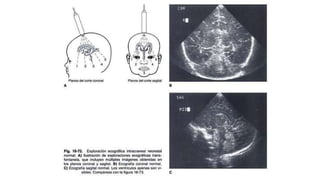

Ultrasonido

Se solicitan US de la cabeza por probables afecciones neurológicas en

los niños. A los bebés prematuros para descartar complicaciones

neurológicas de la falta de maduración, como hemorragia cerebral

(hemorragia intraventricular) o lesiones en la materia blanca del cerebro

que rodea los ventrículos (leucomalacia periventricular)

También se solicitará para bebés que presenten:

un incremento anormal en el tamaño de la cabeza

prominencia de la fontanela

síntomas neurológicos

traumatismo en la cabeza

Los ultrasonidos de la cabeza suelen ayudar a diagnosticar:

hemorragia en el tejido cerebral o los ventrículos

hidrocefalia (exceso de líquido en el cerebro y los ventrículos)

una masa en el cerebro, como un tumor o un quiste

posibles complicaciones de la meningitis